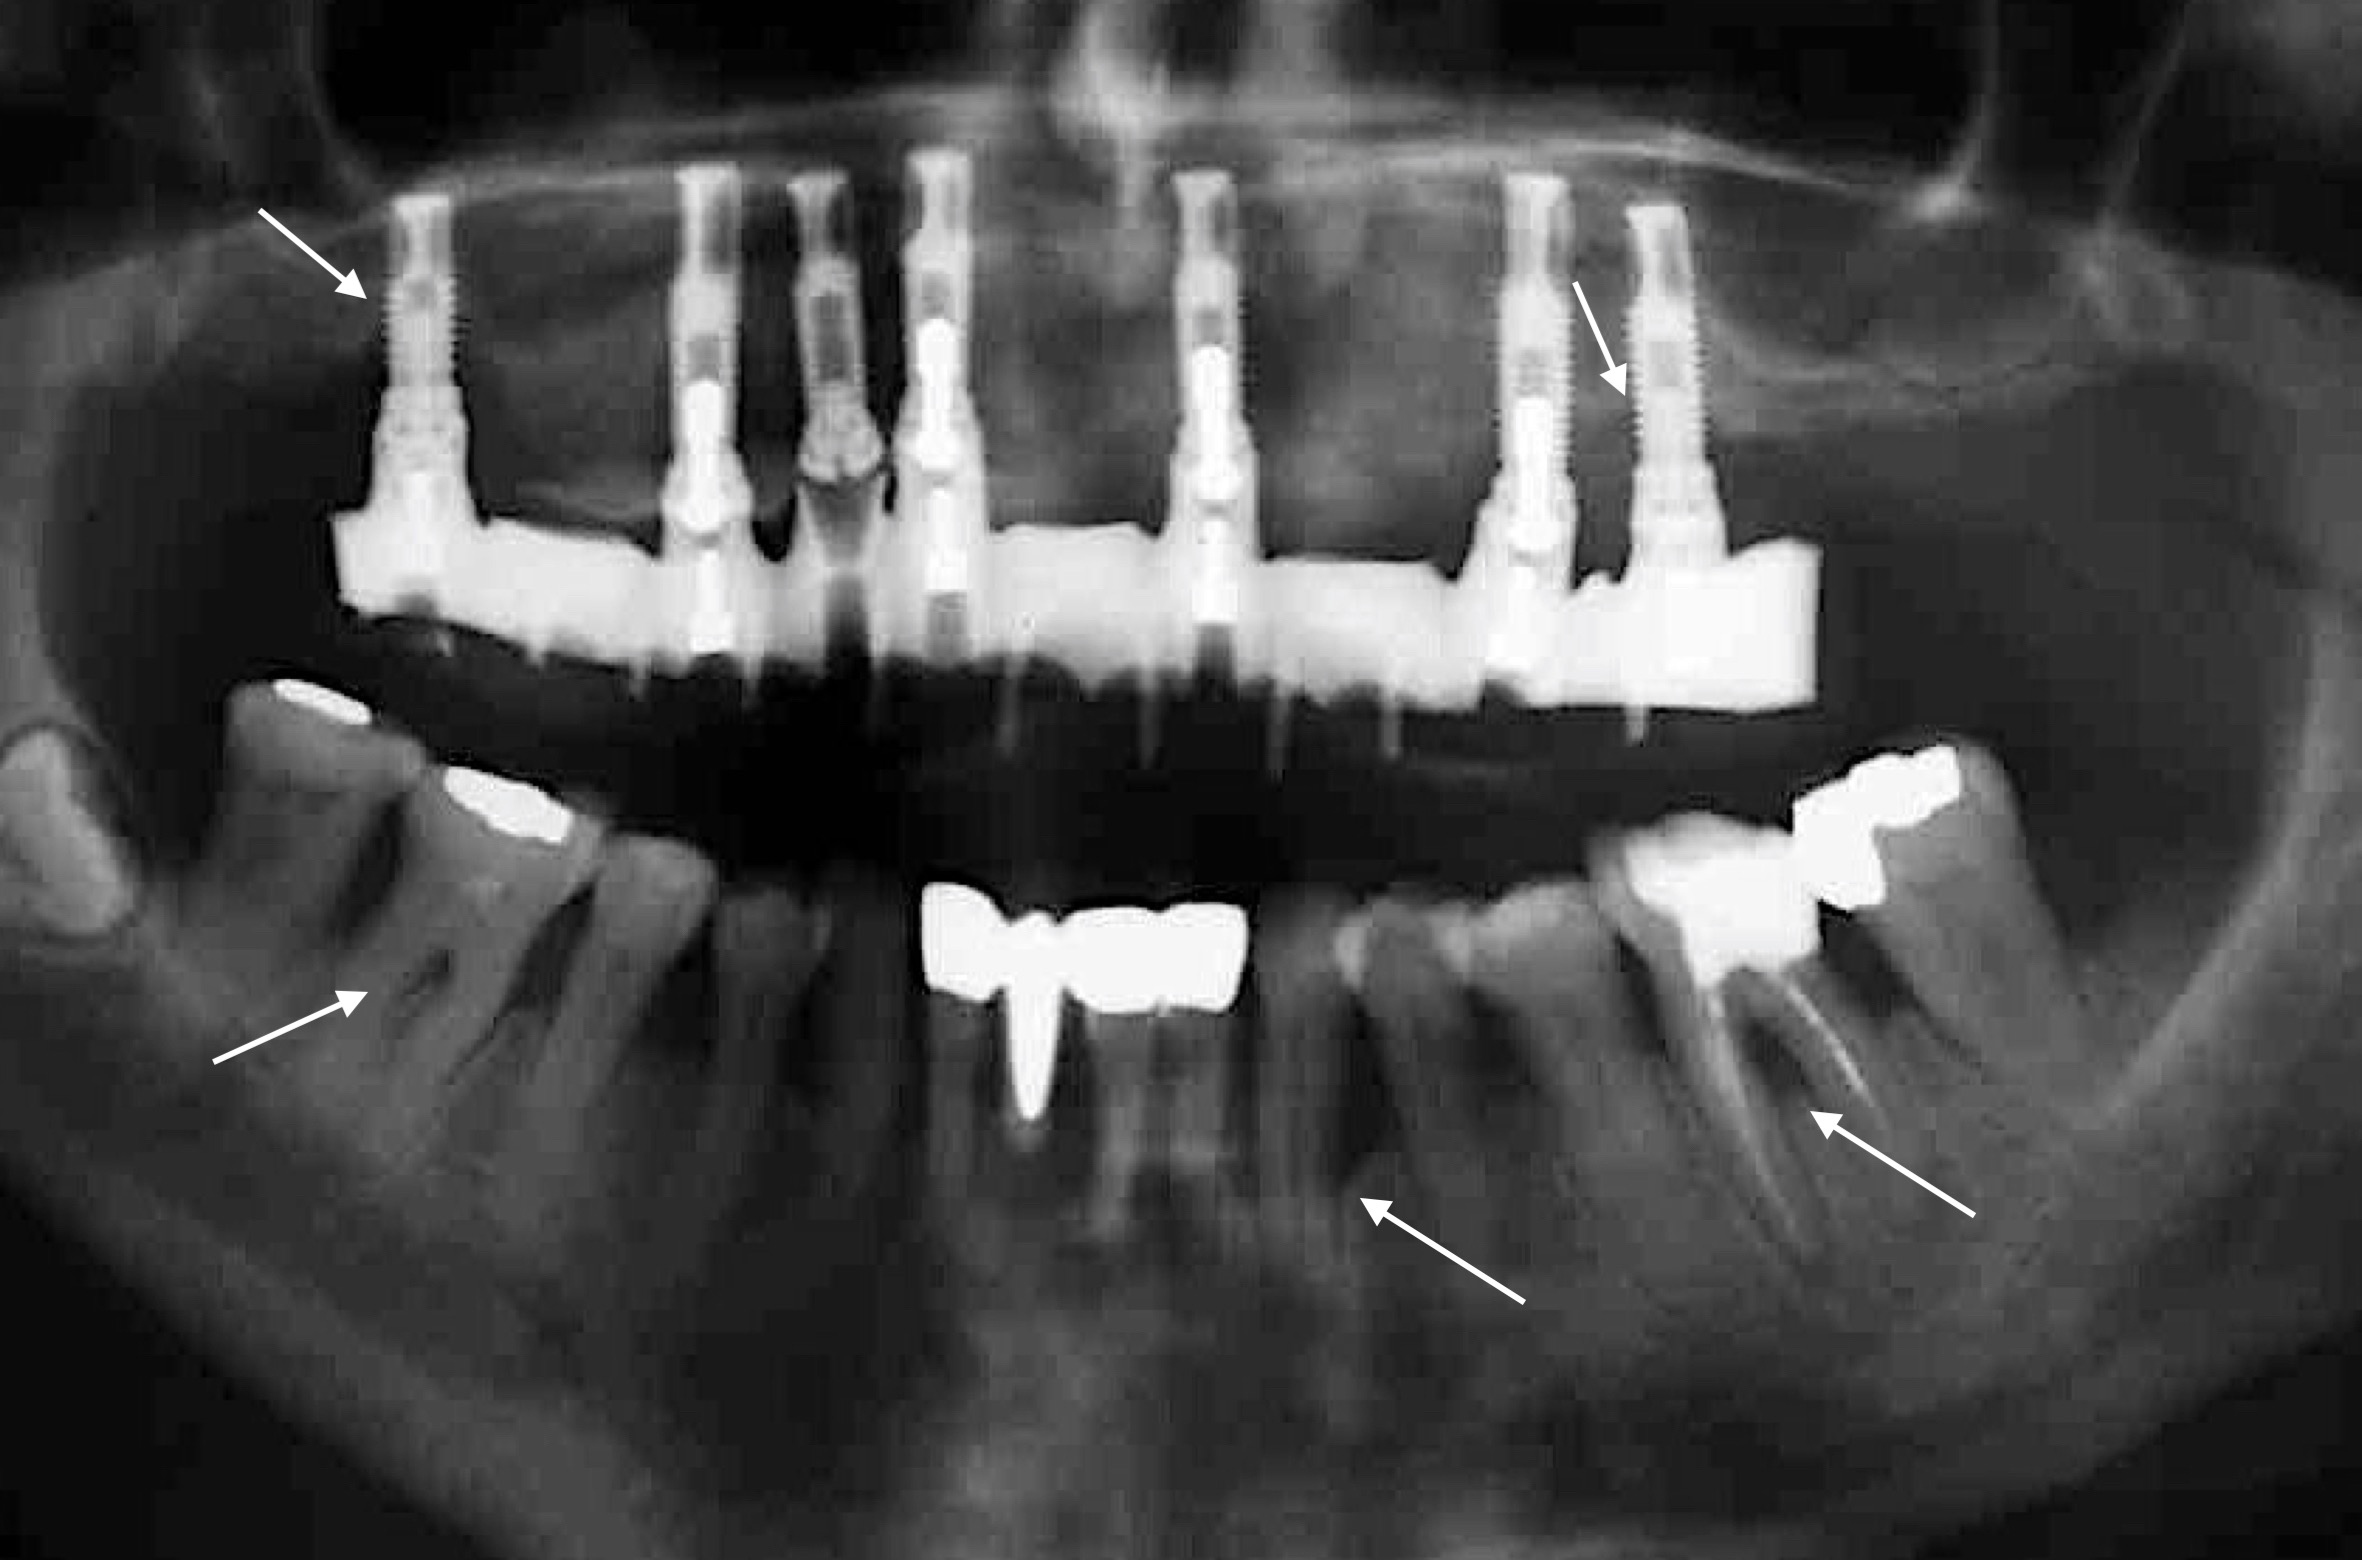

Doch wie hoch ist das Risiko bei Parodontitis-PatientInnen auch eine peri-implantäre Mukositis oder gar Peri-implantitis zu entwickeln und im schlimmsten Fall einen Implantatmisserfolg zu erleiden – kleiner, gleich, oder doch größer …?

Zahlreiche Übersichtsarbeiten der letzten 10 Jahre belegen ein höheres Risiko eines Implantatmisserfolgs bei PatientInnen mit parodontaler Grunderkrankung (z.B.: Renvert & Persson 2009, Sousa et al. 2016, uvm.) und dieses Risiko scheint bei PatientInnen mit der Diagnose „generalisierte aggressive Parodontitis“ noch zusätzlich erhöht zu sein (Monje et al. 2016). Um diese Komplikation möglichst zu vermeiden, gilt es den/die Patienten/Patientin parodontal möglichst gut im Griff zu halten! Das bedeutet: 1) Die parodontale Therapie muss vor der Implantattherapie stattfinden; 2) Strikte Optimierung der Mundhygiene und vor allem gezielte Re-instruktion nach Eingliederung der Implantat-getragenen Versorgung; 3) Planung und Durchführung regelmäßiger Recallsitzungen um einerseits kein Rezidiv in Bezug auf die Parodontitis zu erleiden und andererseits peri-implantäre Erkrankungen frühzeitig zu erkennen; und 4) Rest-Sondierungstiefen nach der parodontalen Therapie möglichst vermeiden! Warum ist letzteres so wichtig? Eine Studie aus Australien (Cho-Yan Lee et al. 2012) hat sehr schön gezeigt, dass das Risiko eine Peri-implantitis zu entwickeln bei Parodontitis-PatientInnen mit Restsondierungstiefen (≥ 6mm Sondierungstiefe) im Vergleich zu Parodontitis-PatientInnen ohne Restsondierungstiefen und parodontal gesunden PatientInnen 4- bis 5-fach erhöht ist!